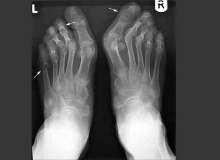

Romatizmalı Hastalar Da Hamile Kalabilir

Hacettepe Üniversitesi Öğretim Üyesi Prof. Dr. Ertenli: Romatizmalı hastaların da hem tedavi olmaya hem gebe kalmaya, çocuk doğurmaya ve çocuklarını emzirmeye hakları vardır. Bunun için hem gebelik hem de süt verme döneminde kullanılabilecek ilaçlar